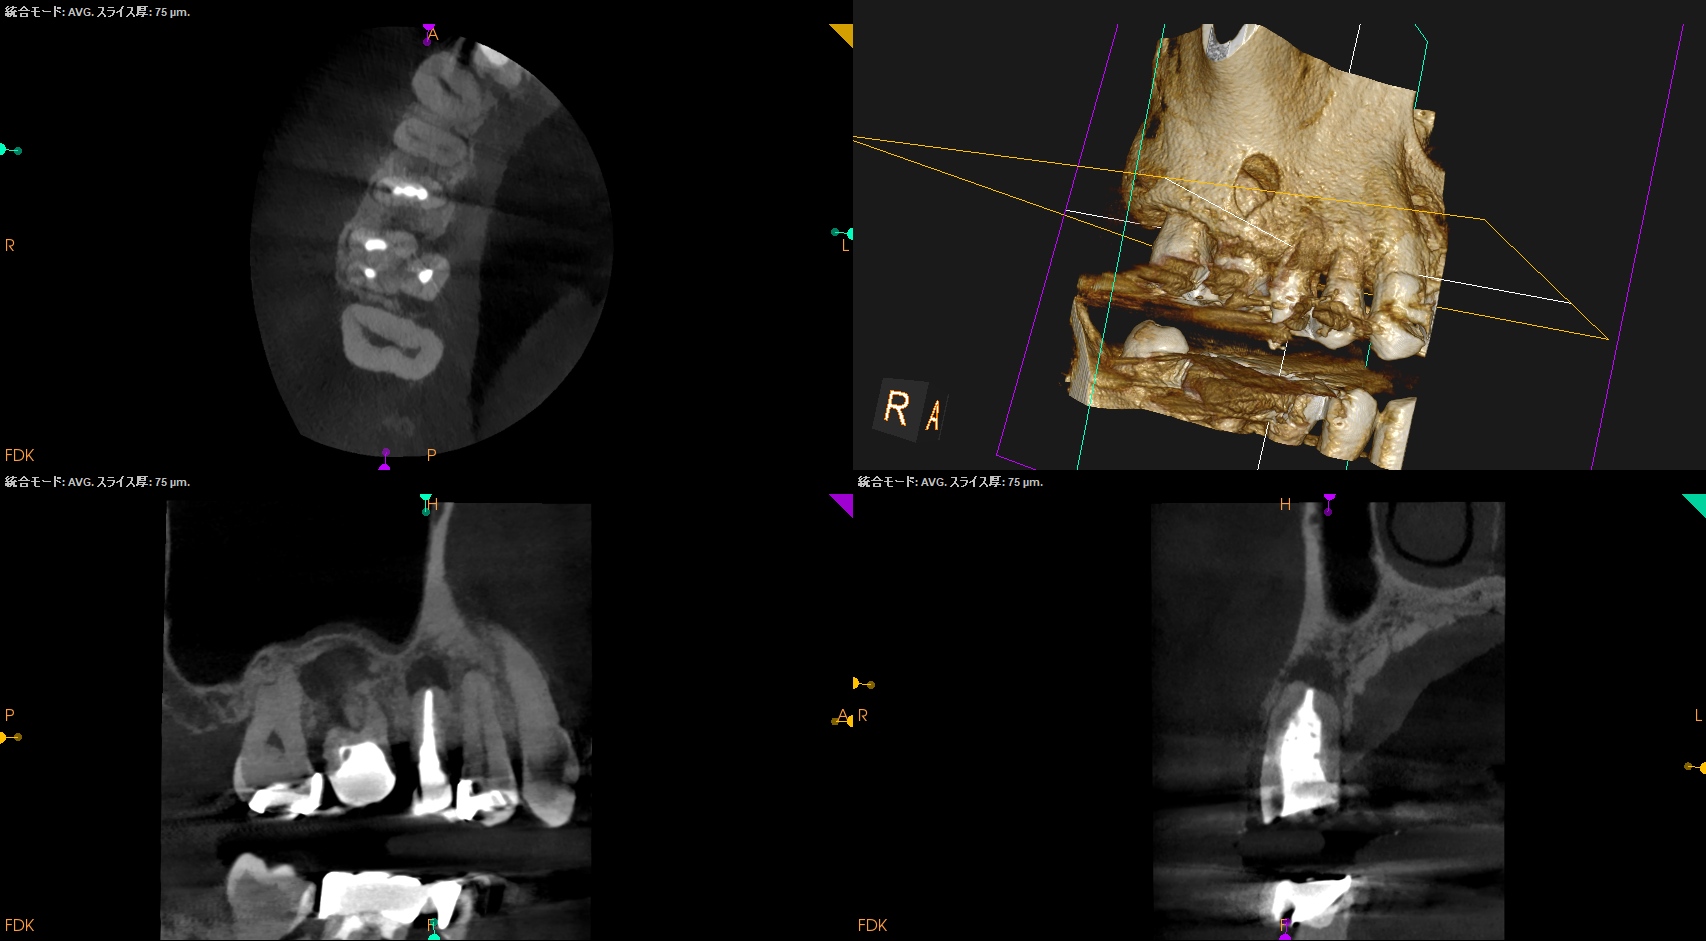

CBCT(2025.9.22)

#4

#3 MB

DB

P

これで抜歯とは…意味がわからない。

このCBCTの絵でこの結果が想像できるだろうか?

このことから何が言えるか?と言えば、

CBCT画像からのみ根尖部の解剖学的形態・状態を推し量るのは無理である

という臨床的事実だ。

再根管治療は実際にFileを根管の中に入れないとそれに意味があるかどうか?はわからないのである。